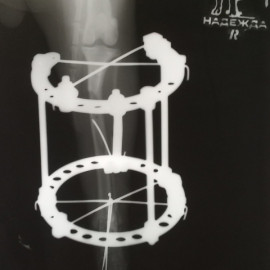

В нашей клинике используется компрессионно-дистракционный аппарат Илизарова!

Ветеринарная клиника "Надежда" использует при проведении ортопедических операций компрессионно-дистракционный аппарат Илизарова.